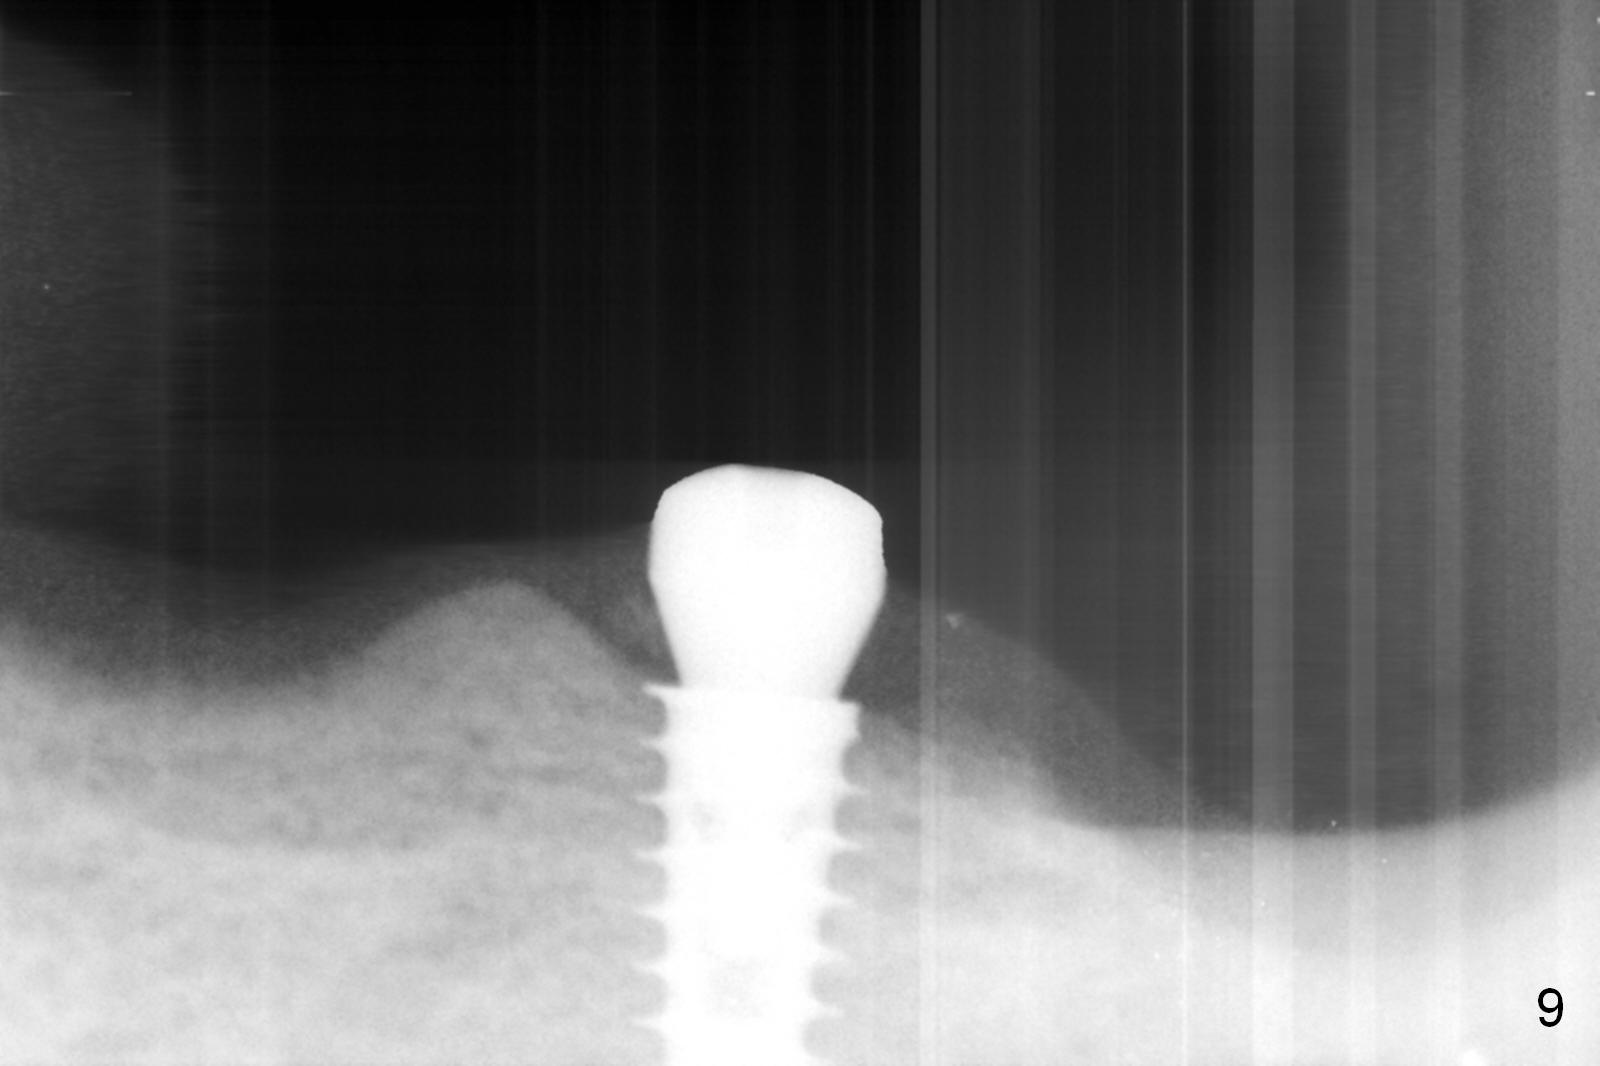

The implant osteointegrates 2 months postop (Fig.9). A pair abutment is placed (Fig.10: 5x4(2) mm) for a provisional (Fig.11). Wax up for final restorations (Fig.12-15). There is no bone resorption 1 year 4 months post cementation (Fig.16). The RPD is doing fine. The implant remains stable 3.5 years post cementation (in spite of open margin), while the other abutment for the RPD (the tooth #30) has mobility with gingival recession.